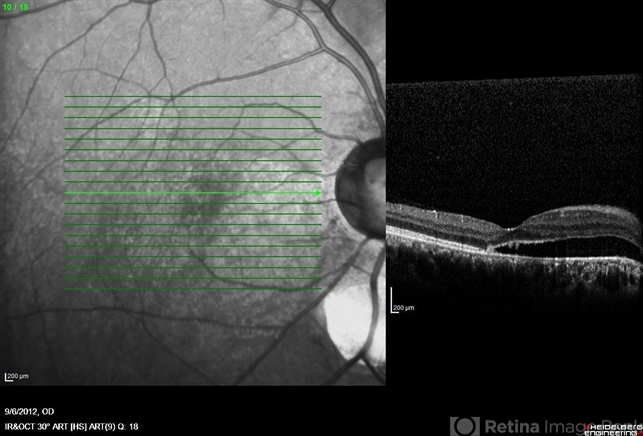

- coloboma of optic disc, coloboma of choroid, optical coherence tomography (OCT), serous retinal detachment

- Heidelberg Spectralis

- OCT image of a 25-year-old woman with serous retinal detachment secondary to coloboma of disc associated with coloboma of choroid.